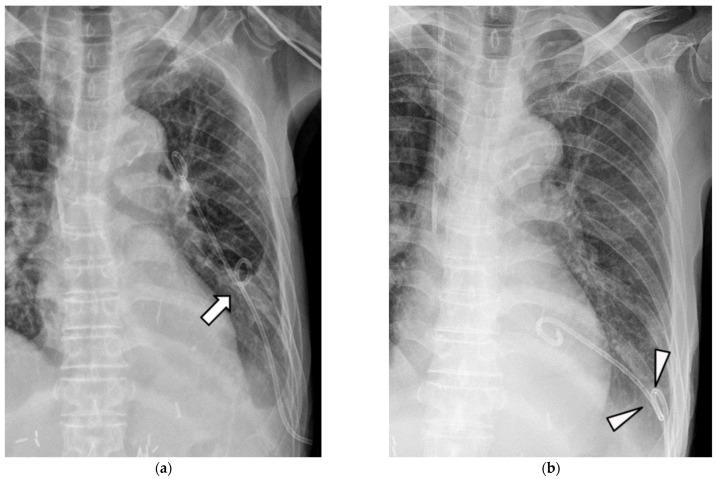

: The novel double-pigtail catheter (DPC) has an additional pigtail coiling at the mid-shaft with multiple centripetal side holes. The present study aimed to investigate the advantages and efficacy of DPC in overcoming the complications of conventional single-pigtail catheters (SPC) used to drain pleural effusion. : Between July 2018 and December 2019, 382 pleural effusion drainage procedures were reviewed retrospectively (DPC, = 156; SPC without multiple side holes, = 110; SPC with multiple side holes (SPC + M), = 116). All patients showed shifting pleural effusions in the decubitus view of the chest radiography. All catheters were 10.2 Fr in diameter. One interventional radiologist performed all procedures and used the same anchoring technique. Complications (dysfunctional retraction, complete dislodgement, blockage, and atraumatic pneumothorax) were compared among the catheters using chi-square and Fisher's exact tests. Clinical success was defined as an improvement in pleural effusion within three days without additional procedures. Survival analysis was performed to calculate the indwelling time. : The dysfunctional retraction rate of DPC was significantly lower than that of the other catheters ( < 0.001). Complete dislodgement did not occur in any of the DPC cases. The clinical success rate of DPC (90.1%) was the highest. The estimated indwelling times were nine (95% confidence interval (CI): 7.3-10.7), eight (95% CI: 6.6-9.4), and seven (95% CI: 6.3-7.7) days for SPC, SPC + M, and DPC, respectively, with DPC showing a significant difference ( < 0.05). : DPC had a lower dysfunctional retraction rate compared to conventional drainage catheters. Furthermore, DPC was efficient for pleural effusion drainage with a shorter indwelling time.